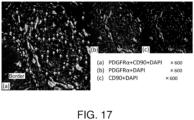

- markers for human mesenchymal stem cells include, but are not limited to, all or some of PDGFR ⁇ positive, PDGFR ⁇ positive, Lin negative, CD45 negative, CD44 positive, CD90 positive, CD29 positive, Flk-1 negative, CD105 positive, CD73 positive, CD90 positive, CD71 positive, Stro-1 positive, CD106 positive, CD166 positive, CD31 negative, CD271 positive, and CD11b negative.

- markers for murine mesenchymal stem cells include, but are not limited to, all or some of CD44 positive, PDGFR ⁇ positive, PDGFR ⁇ positive, CD45 negative, Lin negative, Sca-1 positive, c-kit negative, CD90 positive, CD105 positive, CD29 positive, Flk-1 negative, CD271 positive, and CD11b negative.

- markers for rat mesenchymal stem cells include, but are not limited to, all or some of PDGFR ⁇ positive, CD44 positive, CD54 positive, CD73 positive, CD90 positive, CD105 positive, CD29 positive, CD271 positive, CD31 negative, and CD45 negative.

- cells whose migration is stimulated by an HMGB1 fragment peptide also include, but are not limited to, PDGFR ⁇ -positive cells.

- PDGFR ⁇ -positive cells whose migration is stimulated by an HMGB1 fragment peptide include, but are not limited to, PDGFR ⁇ -positive mesenchymal stem cells, PDGFR ⁇ -positive bone marrow-derived mesenchymal stem cells, and PDGFR ⁇ -positive bone marrow-derived cells which are obtained as adherent cells by means of cell culture of a monocyte fraction of blood obtained by bone marrow collection (bone marrow cell collection) or peripheral blood collection.

- PDGFR ⁇ -positive mesenchymal stem cells include cells that are positive for PDGFR ⁇ and CD44, cells that are positive for PDGFR ⁇ and CD90, cells that are positive for PDGFR ⁇ and CD105, cells that are positive for PDGFR ⁇ and CD29, and such.

- Immunostaining of the myocardial tissue sections was performed using antibodies against PDGFR ⁇ and CD29, which are surface markers of mesenchymal stem cells, to assess whether accumulation of mesenchymal stem cells was observed. Staining of the nuclei was performed using DAPI.

- Immunostaining of the myocardial tissue was performed using antibodies against PDGFR ⁇ , CD90, and CD105, which are surface markers of mesenchymal stem cells, to evaluate whether accumulation of mesenchymal stem cells was observed at the infarct border. Staining of the nuclei was performed using DAPI.